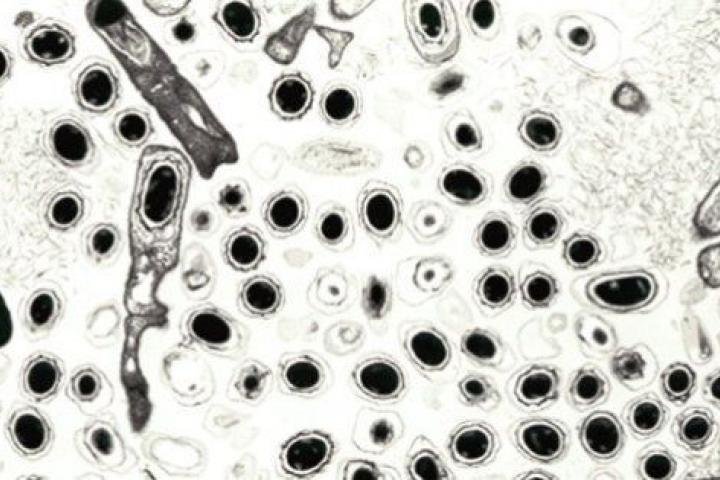

El ántrax es una infección provocada por una bacteria llamada Bacillus anthracis y, en la mayor parte de sus formas, puede ser letal si se inhala. Algunas formas de la enfermedad responden bien al tratamiento con antibióticos y con vacunas.